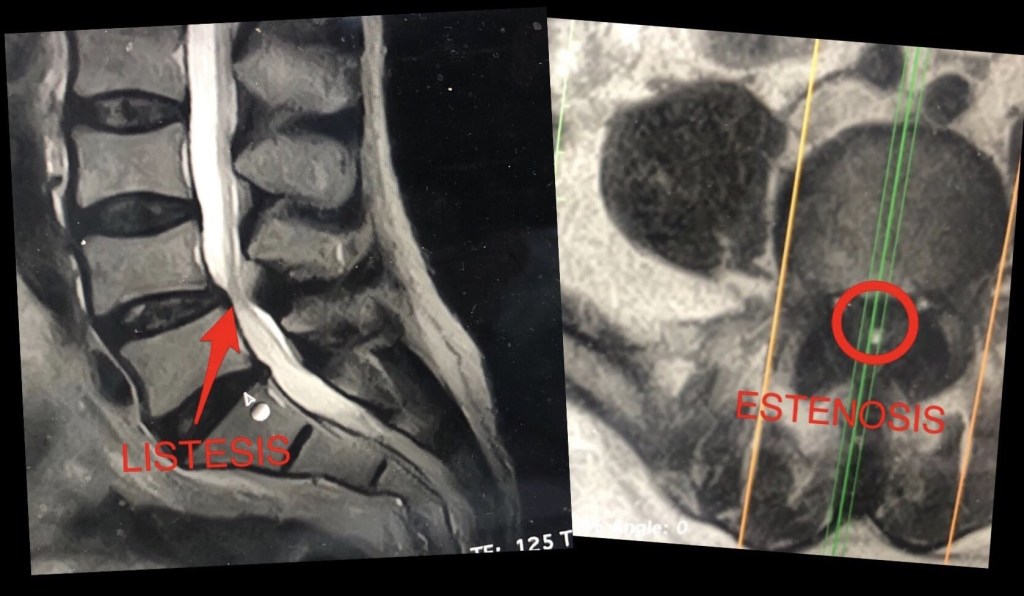

Llamamos estenosis de canal a la compresión u obstrucción que se produce dentro de las vértebras, en el canal que forman éstas y por el que transcurre la médula espinal, la cola de caballo y el conjunto de nervios raquídeos que se originan de ella.

Ese canal que forman las vértebras se puede obstruir cuando se produce un desplazamiento de las estructuras, por ejemplo, en la espondilolistesis o también cuando alguna de ellas sale de su sitio o protruye, como es el caso de las hernias de disco.

Una variante de estenosis es la estenosis foraminal, que es la que se produce cuando los discos vertebrales o el complejo que forman las articulaciones facetarias de unas vértebras y otras, se ve obstruido por una inflamación o algún elemento anatómico extraño.

La estenosis produce un conflicto de espacio en el que algunas estructuras se ven comprometidas, dañadas, y por tanto, genera una respuesta dolorosa, casi siempre de características neuropáticas. Este dolor irradiado, nosotros lo denominamos neuralgia, cuando afecta a las raíces que se dirigen a los miembros inferiores